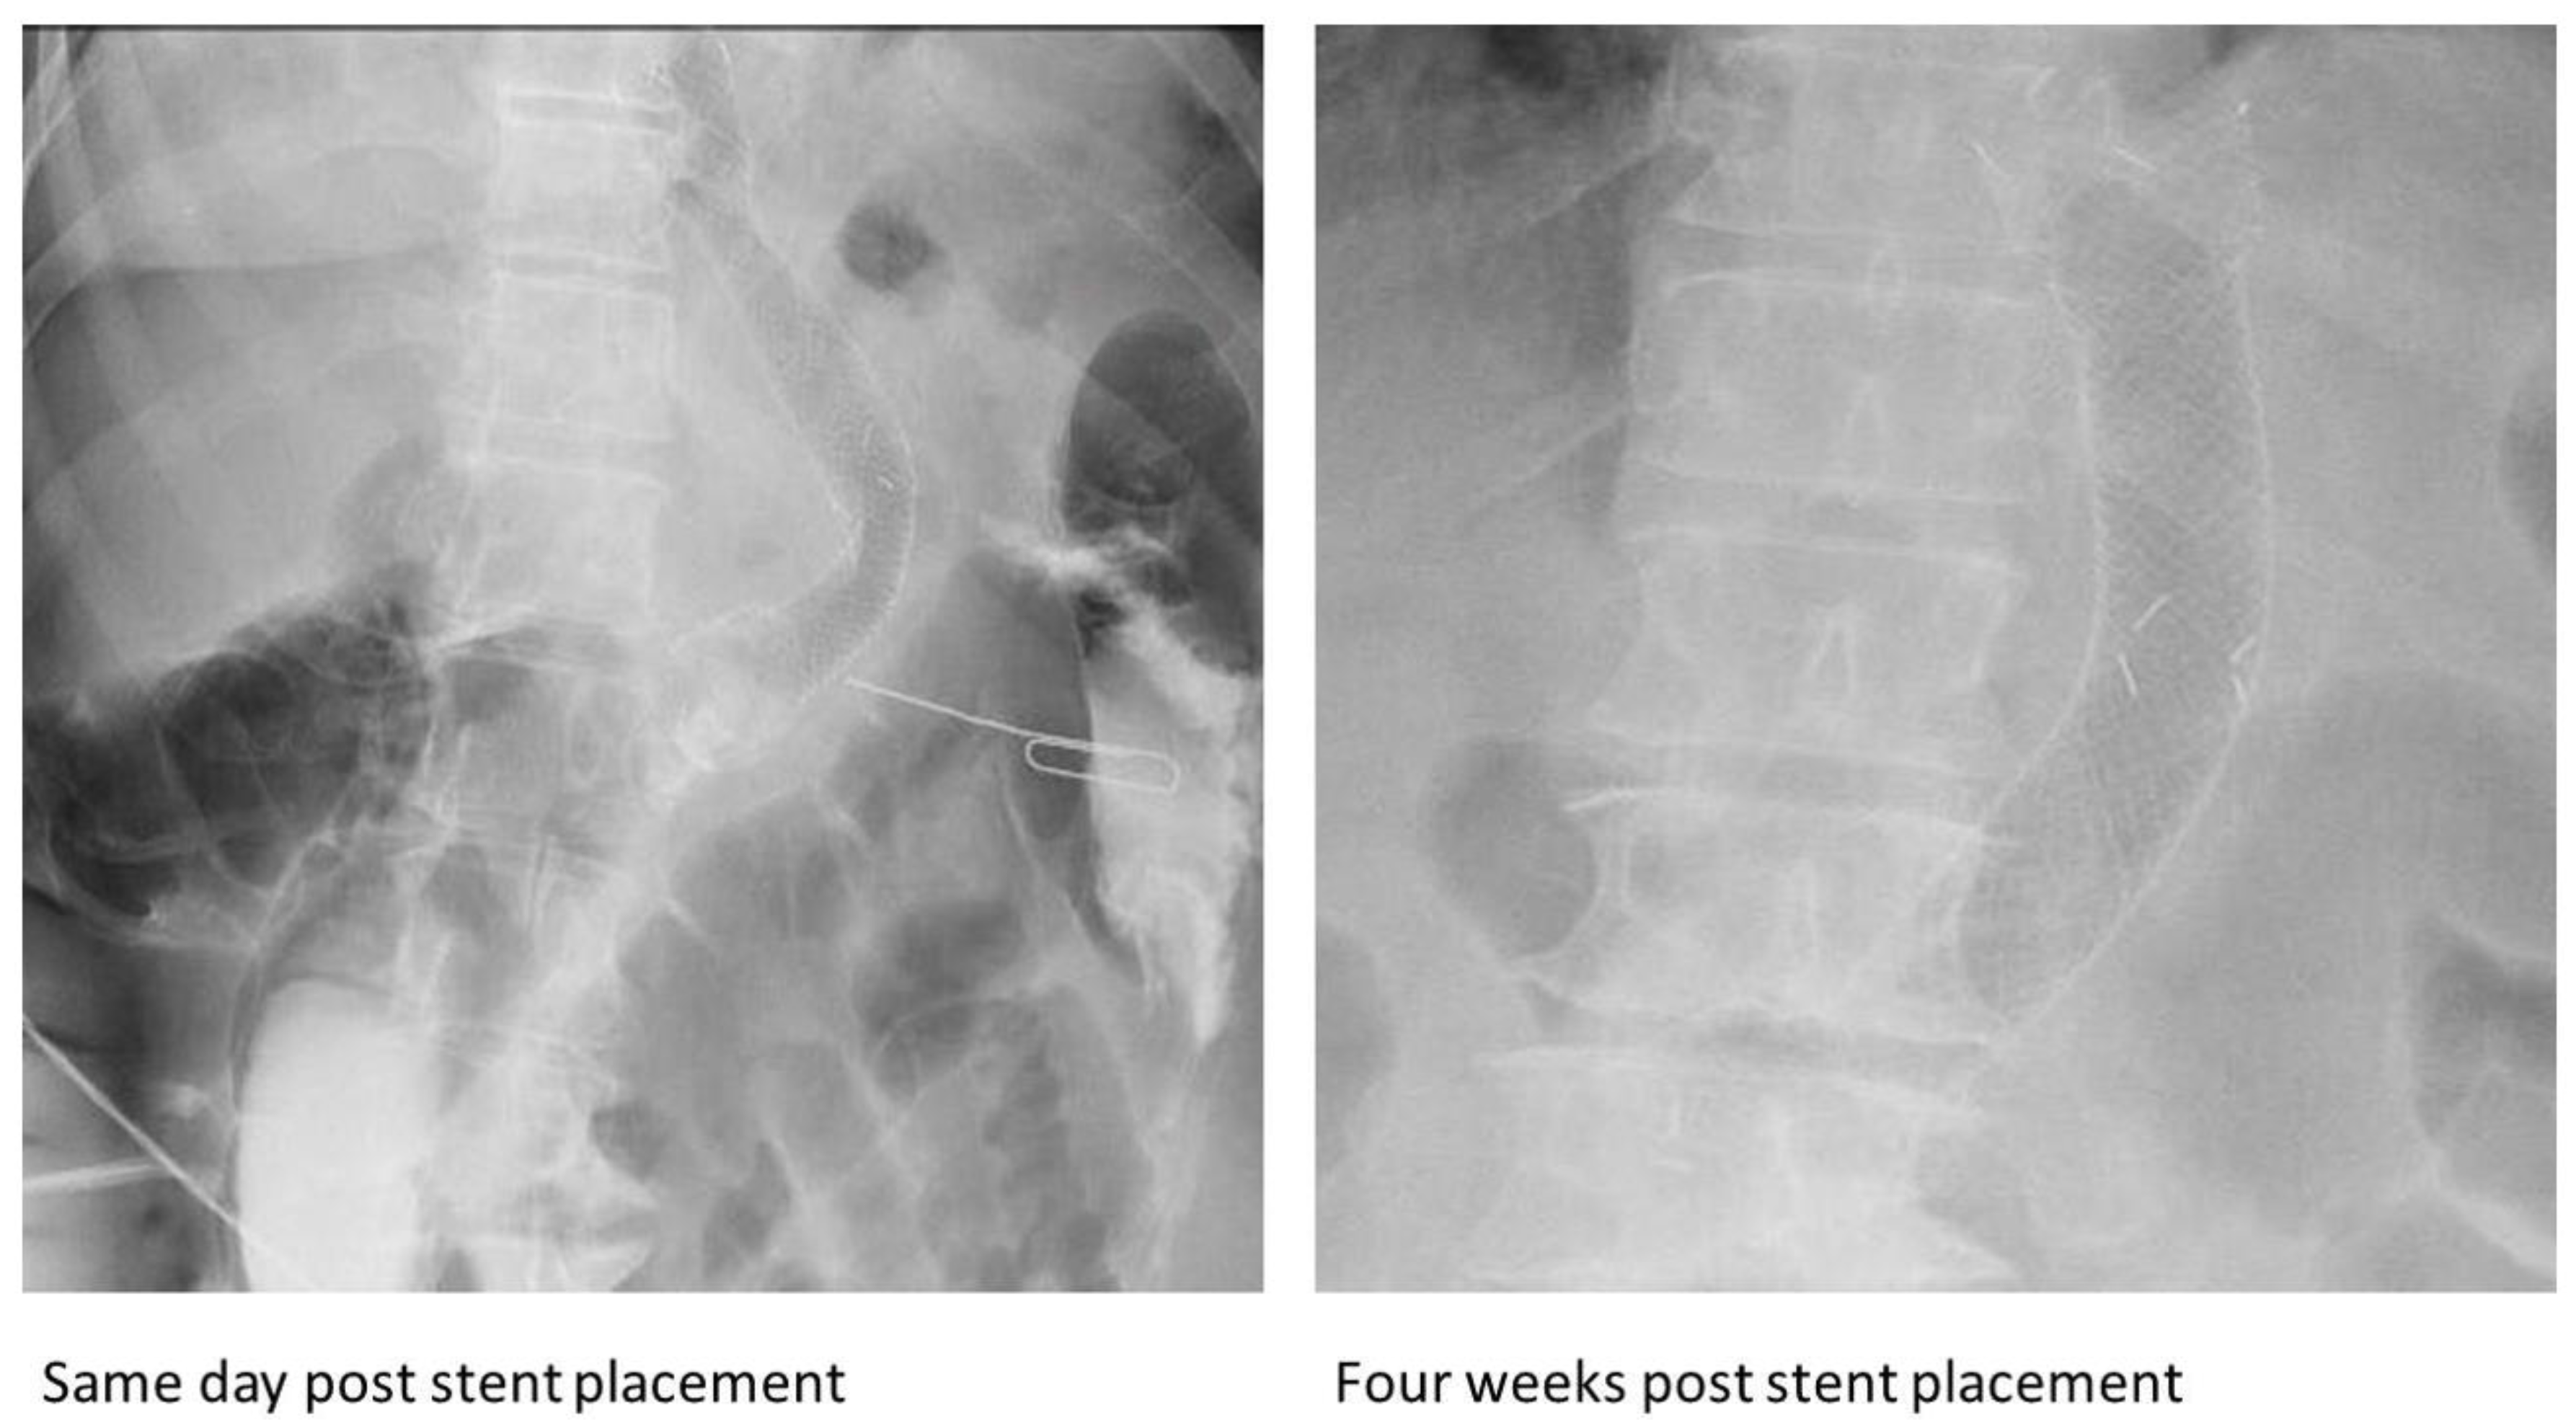

| Some cases were diagnosed by imaging [8,9,11,12,13,16,20,24,32] Most were diagnosed during or after endoscopic removal | All the SEMS fractured in vivo and were noted during or after endoscopic removal. | ||

| All our cases underwent endoscopic removal. Our third and sixth cases were managed using a gastric overtube to ensure mucosal protection and prevent fluid leaks. Overtube-assisted retrieval of foreign bodies including esophageal stents has been reported prior [47,48]. However, the endoscopic technique used to manage the impaled SEMS in our third case was unique, as the overtube was synchronously advanced with stent extraction, resulting in a safe and smooth removal as demonstrated in Video S1. Moreover, the proximal part of the stent in the sixth case was inverted inwardly, allowing for safe downward pushing of the fractured stent into the stomach. These techniques can aid future endoscopists in safely removing a fractured stent from the stomach | |||